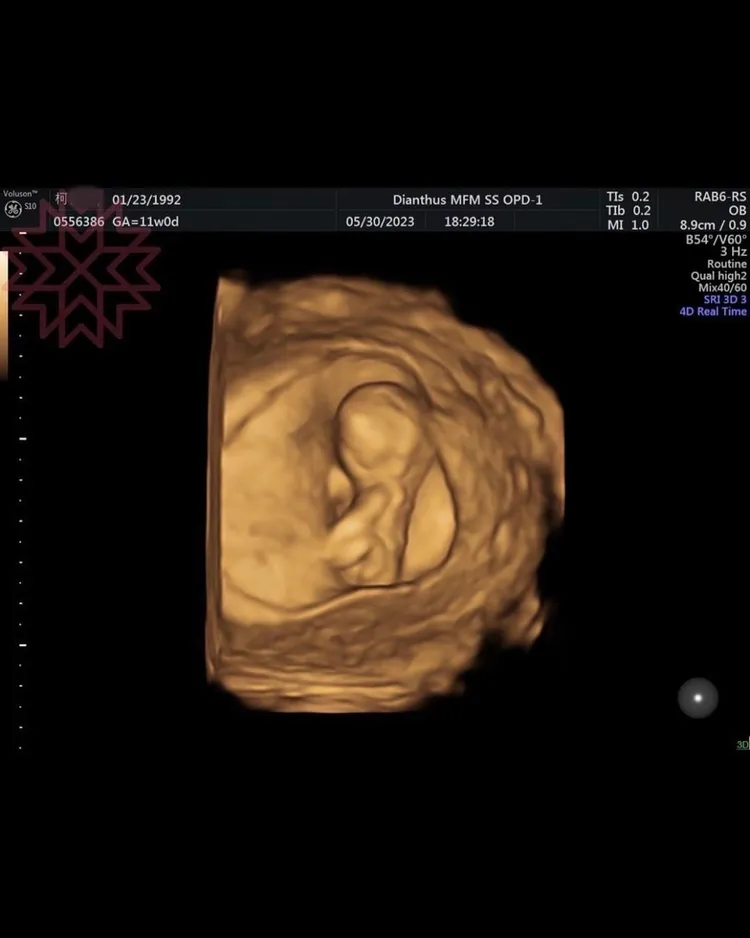

楊繡惠日前在臉書貼出兩張寶寶的超音波照,上頭顯示寶寶目前11周,看起來相當健康。她開心地寫下「哈哈,恭喜我吧!滿3個月再公開!」雖有眼尖網友發現,超音波左上角有媽媽的出生日期,認為是楊繡惠的親人懷孕,但也有不少人打趣問「是不是白雲哥的?」「恭喜小白雲誕生了,真是愛的結晶!」